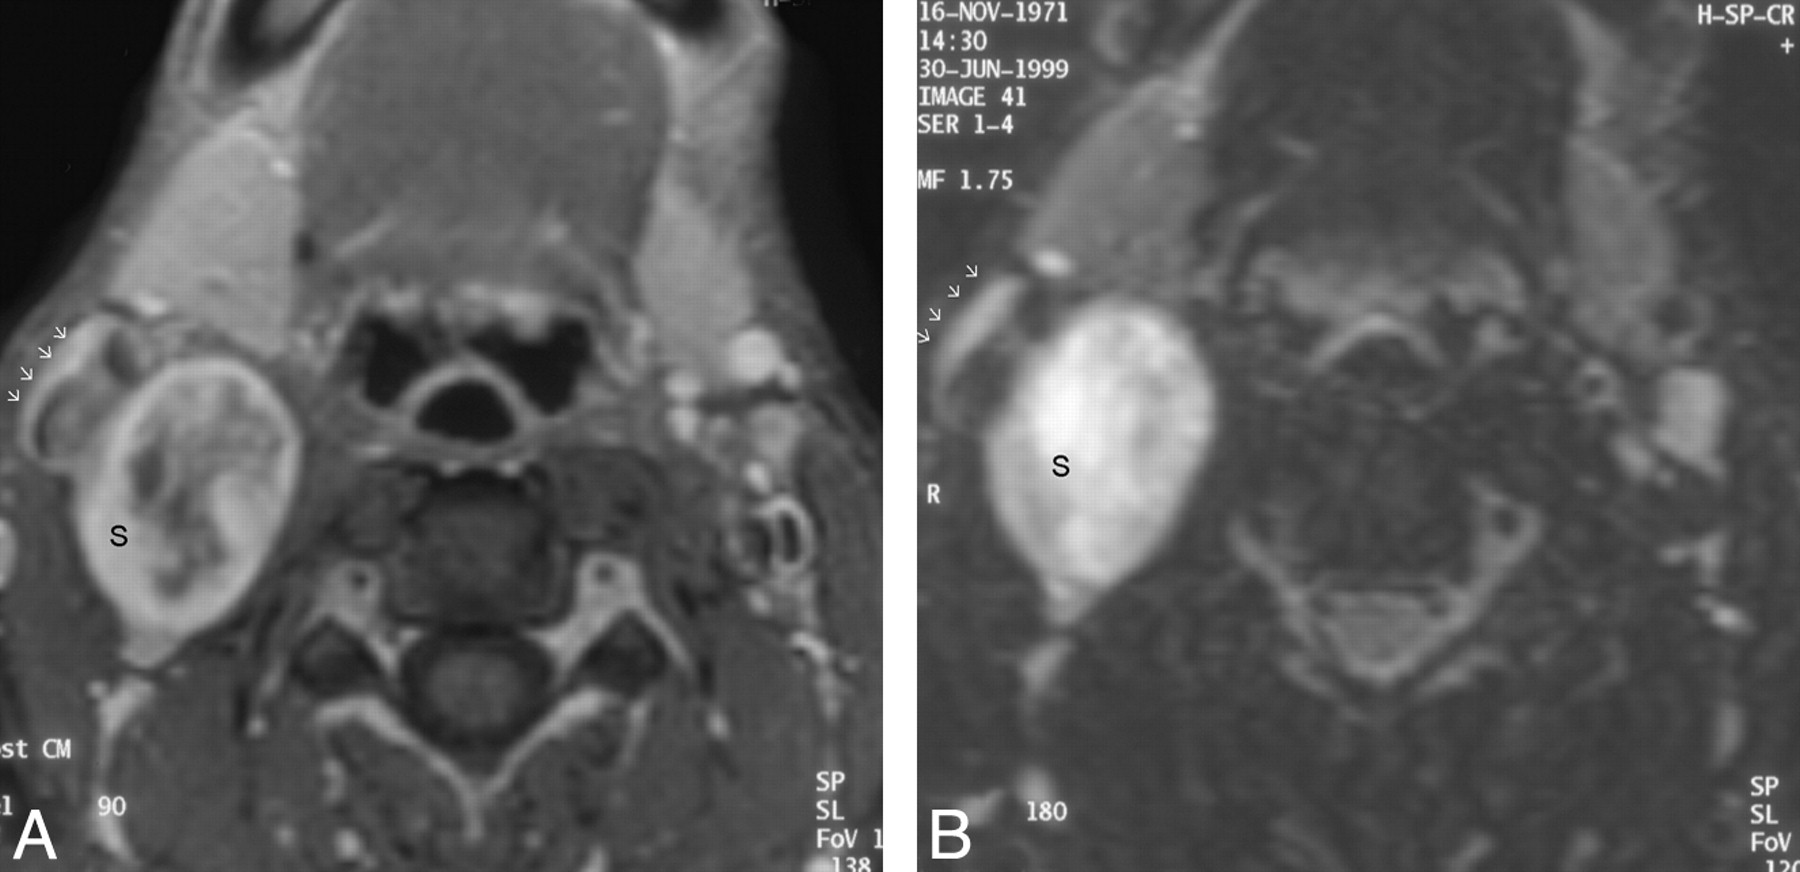

The schwannoma shows intense heterogeneous enhancement on the postgadolinium fat-saturated T1WI (A) and appears heterogeneously bright on the fat-saturated T2WI (B). The nonenhancing areas in the center of the mass correspond to the areas of fluid signal intensity seen in the T2WI. The entire carotid sheath (arrows) is displaced in an anterolateral direction.

In the literature, schwannomas have been described as hypo-, iso-, or hyperattenuated (Fig 1), with variable texture (heterogeneous or homogeneous) and enhancement on CT.(10,11) The heterogeneity has been attributed to cystic degeneration, xanthomatous change, or areas of relative hypocellularity adjacent to densely cellular or collagenous regions.(12) More than half of the schwannomas (58%) encountered in this study had a heterogeneous texture; however, some of this may be due to patchy enhancement (there were no unenhanced images for comparison). Lack of information on the interval between image acquisition and contrast injection was among the drawbacks of this retrospective analysis. Still, in 2 patients, there was marked heterogeneity and obvious areas of cystic changes, which were supported by corresponding MR imaging findings. Schwannomas are hypovascular tumors, but if images are acquired beyond the first 60 seconds after the contrast injection, they can show marked enhancement due to pooling of contrast from poor venous drainage, simulating a hypervascular lesion.(2,13) The different patterns of contrast enhancement seen during this study can be explained by the aforementioned postcontrast enhancement dynamics. The MR imaging findings of low-to-intermediate signal intensity on T1WI, heterogeneous hyperintensity on T2WI, and intense heterogeneous postgadolinium enhancement (Fig 2) are consistent with the standard teachings on schwannomas.(2,11)

Our results regarding the average size, margin, appearance, and location within the lateral neck of SCSCs are concordant with those of the literature. The anterior displacement of parapharyngeal fat and the medial displacement of the visceral space (Fig 3), as demonstrated in most of the patients from this study, are typical of a carotid space lesion.(5,10) The anterior displacement of the ICA seen in 75% of our patients is comparable with the findings in earlier studies on nerve sheath tumors of the carotid space.(11,13) By virtue of the anatomic location of the sympathetic chain, posteromedial to the carotid sheath, SCSCs tend to displace the ICA and CCA in an anterior and lateral direction (Figs 1 and 2).(5)